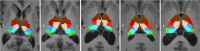

The thalamus is an essential relay station in the cortical-subcortical connections. It is characterized by a complex anatomical architecture composed of numerous small nuclei, which mediate the involvement of the thalamus in a wide range of neurological functions. We present a novel framework for segmenting the thalamic nuclei, which explores the orientation distribution functions (ODFs) from diffusion magnetic resonance images at 3 T. The differentiation of the complex intra-thalamic microstructure is improved by using the spherical harmonic (SH) representation of the ODFs, which provides full angular characterization of the diffusion process in each voxel. The clustering was performed using the k-means algorithm initialized in a data-driven manner. The method was tested on 35 healthy volunteers and our results show a robust, reproducible and accurate segmentation of the thalamus in seven nuclei groups. Six of them closely matched the anatomy and were labeled as anterior, ventral anterior, medio-dorsal, ventral latero-ventral, ventral latero-dorsal and pulvinar, while the seventh cluster included the centro-lateral and the latero-posterior nuclei. Results were evaluated both qualitatively, by comparing the segmented nuclei to the histological atlas of Morel, and quantitatively, by measuring the clusters' extent and the clusters' spatial distribution across subjects and hemispheres. We also showed the robustness of our approach across different sequences and scanners, as well as intra-subject reproducibility of the segmented clusters using additional two scan-rescan datasets. We also observed an overlap between the path of the main long-connection tracts passing through the thalamus and the spatial distribution of the nuclei identified with our clustering algorithm. Our approach, based on SH representations of the ODFs, outperforms the one based on angular differences between the principle diffusion directions, which is considered so far as state-of-the-art method. Our findings show an anatomically reliable segmentation of the main groups of thalamic nuclei that could be of potential use in many clinical applications.